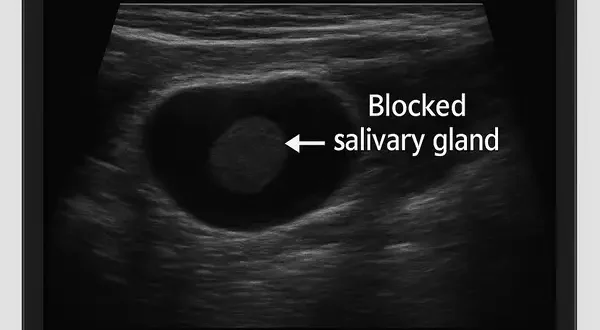

Blocked Salivary Gland: Causes and Treatment

Ultrasound view used to diagnose a blocked salivary gland, illustrating how modern imaging helps detect and treat gland obstruction effectively.

A blocked salivary gland may sound like a minor inconvenience, but when one of these tiny ducts gets clogged, it can turn a pleasant lunch into a painful